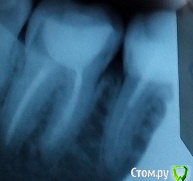

Sloboda Опубликовано 20 февраля, 2017 Поделиться Опубликовано 20 февраля, 2017 Здравствуйте! Проблема такая: был пролечен по пульпиту 36 зуб, запломбированы каналы, поставлена пломба и штифт. Зуб до этого не болел и вообще никак не беспокоил, просто было затемнение рядом со старой цементной пломбой - решили пломбу поменять - под ней сюрприз - хронический пульпит. Через месяц после лечения зуб стал реагировать при приеме пищи (реакции только на нагрузку; реакции на температуру отсутствовали и отсутствуют вообще) - слабо пульсировать. Стоматолог сказал, что это нормально и должно само пройти. В течении полугода, такие пульсации при приеме пищи в зубе проявлялись периодически, но сильно не беспокоили. На очередном приеме, на жалобы по поводу пульсации 36 зуба, стоматолог сказал, что, возможно, это из-за завышенной пломбы - пломбу подпилили. И вот уже 4 дня зуб сильно болит следующим образом: при притрагивании к зубу языком/пальцем возникает сильная пульсирующая боль, невозможно сомкнуть челюсть, жевать на стороне больного зуба невозможно, припухла десна, также опух лимфоузел на стороне больного зуба. Соседние зубы - 7 (также пролечен по пульпиту много лет назад) и 5 никак не реагируют, на них можно спокойно жевать и т.д. Т.е. локализация боли чисто в 36 зубе. Делали рентген 36 зуба, врач сказал, что все прекрасно, периодонтита нет, каналы пролечены хорошо. Стучали по зубу (и с верху, и с боку) - болевой реакции нет. Проверяли прибором каким-то проводящим электричество (не помню как называется), сказали, что остатков нерва нет, т.к. нет никакой болевой реакции при подаче тока нет. Но зуб-то продолжает болеть! Боль несколько снизилась после принятия ципролета (2 таблетки). Врач сказал, что это скорее всего или десна или опять же, завышенная пломба (пломбу подпилили еще раз), но если боль не пройдет - придется зуб вскрывать. На мой взгляд, есть непролеченный участок в канале, думаю, это он воспалился + симптомы очень сильно похожи на периодонтит. Хотелось бы узнать ваше мнение - что это такое и что с эти делать. Заранее благодарю за помощь. К сожалению, снимков лучшего качества пока нет, т.к. формат rvg нигде не открывается, завтра приложу скриншот улучшенной версии снимка. На первом снимке, сделанном на пеленку видна только часть 36 зуба), сам снимок был сделан полгода назад. Второй снимок сделан сегодня. Ссылка на комментарий